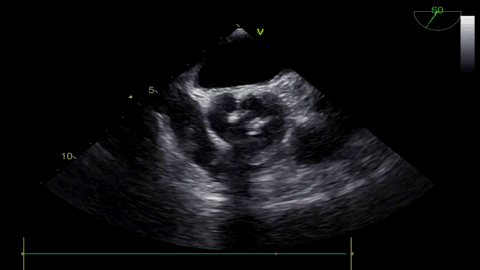

术前超声:

球扩后超声

发生瓣叶切割,无窦侧瓣叶切割,Type0结构形变为类三叶瓣结构。